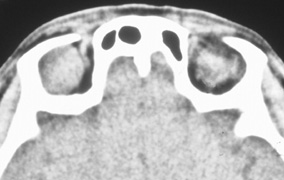

Fig. 14. A,B. Large intraorbital lymphangioma causing proptosis and optic nerve compression in a 2-year-old child. C. View of the left orbit from above after removal of the frontal bone flap, including the supraorbital rim and orbital roof. An extensive exposure of the entire superior and lateral orbit is afforded. The levator and superior rectus complex is being retracted laterally with a muscle hook, whereas the Freer elevator retracts the superior oblique muscle medially. The frontal nerve can be seen running from posterior to anterior over the superior orbit. The orbital mass is exposed in this fashion. D. The fronto-orbital bone flap is wired back in place after completion of the procedure. E. Postoperative appearance of the patient. F. The postoperative CT scan shows complete removal of the lymphangioma. This large and diffuse lesion would have been difficult to remove with any other approach.

A burr hole is placed in the midline just above the orbital rim. This burr hole usually enters the frontal sinus. A second burr hole is placed anteriorly in the temporalis fossa at the junction of the cranium and orbit so that both compartments are exposed. Two or three additional holes are made in the frontal bone connecting the first two holes. The orbital rim is cut from the midline inferiorly, and the lateral orbital rim is cut from the temporalis fossa anteriorly. The dura is freed from the undersurface of the bone flap and is elevated superiorly, and the orbital roof is cracked off. The frontal bone, orbital roof, and supraorbital rim break off in one piece. The brain is retracted superiorly, and the remaining orbital roof is removed with bone rongeurs (see Fig. 14C).

After removal of the bony roof, the periorbita is visible. Typically, the periorbita is thin, and the levator rectus muscle and frontal nerve are visible beneath it. If exposure of the posterior optic nerve is desired, the dura can be elevated over the optic canal. The canal can be unroofed to decompress or explore the optic nerve, and the dura may be opened to view the intracranial optic nerve and the chiasm. At the orbital apex, the annulus may be cut to allow more anterior dissection and removal of the optic nerve in cases such as optic nerve glioma or meningioma. Because the superior orbital fissure and its contents lie lateral to the nerve, the intraconal space is entered on the medial side of the optic nerve. The orbital dissection can be carried out with a minimal amount of brain retraction after the en bloc removal of the frontal bone, supraorbital rim, and orbital roof.

After the dissection, the dura is closed and the frontal bone flap is plated or wired back into position (see Fig. 14D). The orbital roof is functionally restored with the replacement of the bone flap. The sinuses must be sealed off with muscle, pericranium, or other tissue. The coronal flap is closed in layers. The postoperative appearance is unchanged because the bone flap is replaced in one piece. Problems with globe ptosis, enophthalmos, pulsatile proptosis, or meningitis are rare. However, extensive mobilization of the temporalis may result in cosmetically significant temporal atrophy. Orbital apical dissection often results in extraocular motility dysfunction as a result of traction on the third, fourth, or sixth cranial nerves, but cranial nerve function usually recovers unless the nerves have been transected.